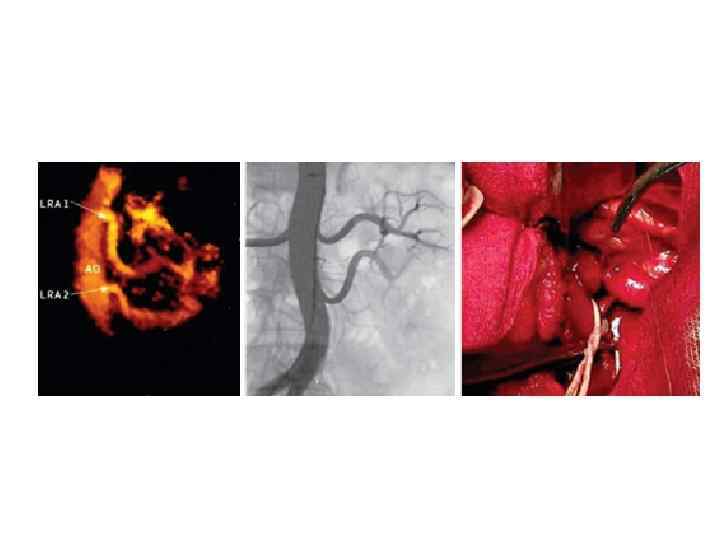

КТ-ангиография брюшной аорты, её ветвей, почек (с внутривенным болюсным введением контрастного вещества).

МСКТ с внутривенным контрастированием брюшного отдела аорты. Кальциноз и аневризматическое расширение аорты, стеноз правой почечной артерии со снижением кровотока в правой почке

КТ- и МРТ-ангиография

Рентгеновская ангиография сосудов почек

КТ сосудов почки

МРТ сосудов почек